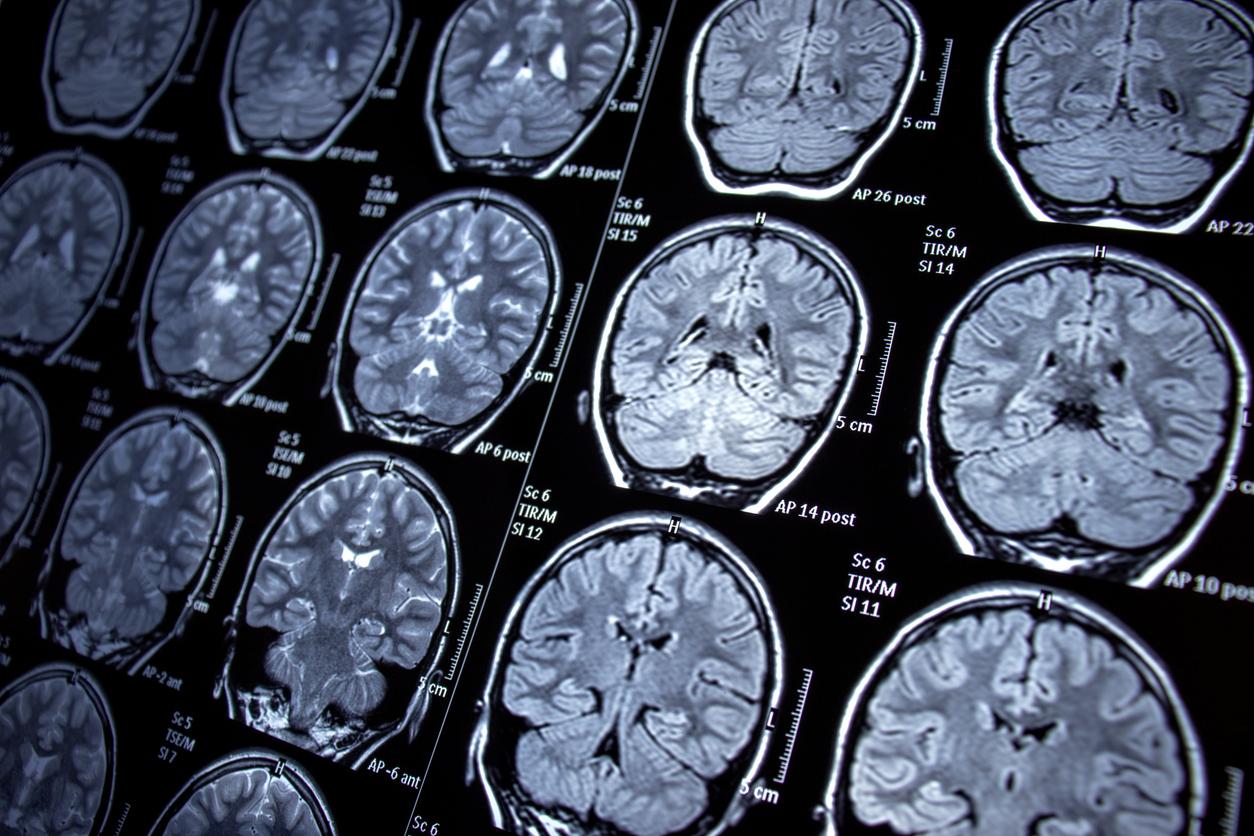

Sur les IRM, les microhémorragies cérébrales apparaissent sous forme de petites lésions. Elles sont considérées comme des marqueurs précoces de lésions cérébrales. Plusieurs recherches ont mis en avant leurs liens avec les accidents vasculaires cérébraux symptomatiques et la démence, avec une prévalence allant de 3 % chez les adultes d'âge moyen à 23 % chez les personnes âgées. Les microhémorragies cérébrales peuvent survenir en cas d’hypertension, de dyslipidémie, de diabète et de maladies cardiovasculaires et cérébrovasculaires. Le tabagisme est également un facteur de risque. Dans une récente étude, des chercheurs du Korea University Ansan Hospital se sont demandés si l’apnée du sommeil pouvait augmenter le risque de microhémorragies cérébrales.

Les microhémorragies cérébrales, des zones focales de moins de 10 mm avec un signal très faible

Les microhémorragies cérébrales ont été identifiées comme des zones focales de moins de 10 mm avec un signal très faible, mesurées par un radiologue ignorant le statut d'apnée du sommeil des volontaires. Cette évaluation a été faite au début de l’étude et quatre ans plus tard. Durant l’analyse des données, les auteurs ont pris en compte l'âge, le sexe, le niveau d'éducation, l'indice de masse corporelle, le niveau d'activité physique, le statut tabagique et de consommation d'alcool, le taux de cholestérol total et de cholestérol LDL, l'hypertension, le diabète, les modifications de la substance blanche liées à l'âge, la variation de l'indice d'apnées-hypopnées, la variation de l'indice de masse corporelle et la pression artérielle.